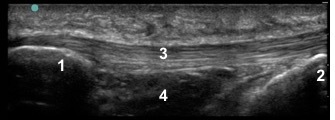

Knee Infrapatellar Tendon Anatomy 1 Image

1. Inferior Patellar (or Inferior Patellar Pole)

2. Tibial Tuberosity

3. Patellar Tendon

4. Hoffa’s Fat Pad